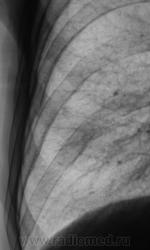

В связи с появившейся осиплостью голоса пациенту была проведена томография гортани.

3. Исследование.